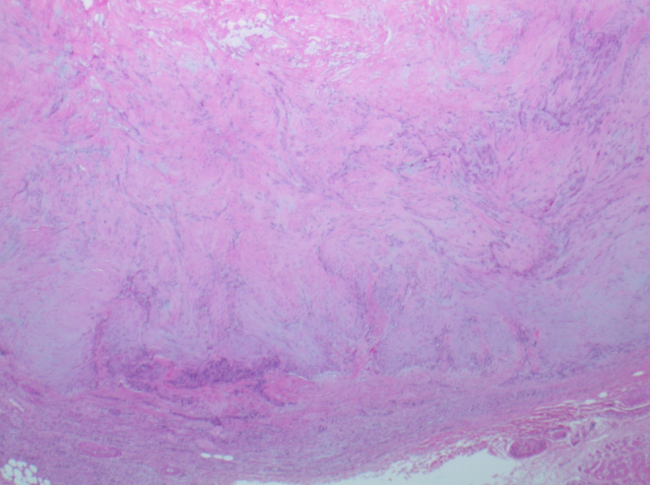

The patient elected to have the mass removed after a full, detailed discussion of conservative and surgical options. Surgically, we made a curvilinear incision along resting skin tension lines, exposing the plantar fat pad. Blunt and sharp dissection deepened the incision to the plantar aspect of the flexor hallucis longus tendon, and allowed visualization of the mass. Once fully exposed, we excised the tumor, which was consistent with the MRI report. It was encapsulated, measured 3.3 x 1.8 x 1.0 cm, and presented with central hyaline degeneration and infarction. After irrigation, we performed the remaining soft tissue closure in layers, with a small drain placed to prevent possible hematoma formation. The postoperative course involved four-to-six weeks of guarded weight-bearing in surgical shoe, with limitations on driving.